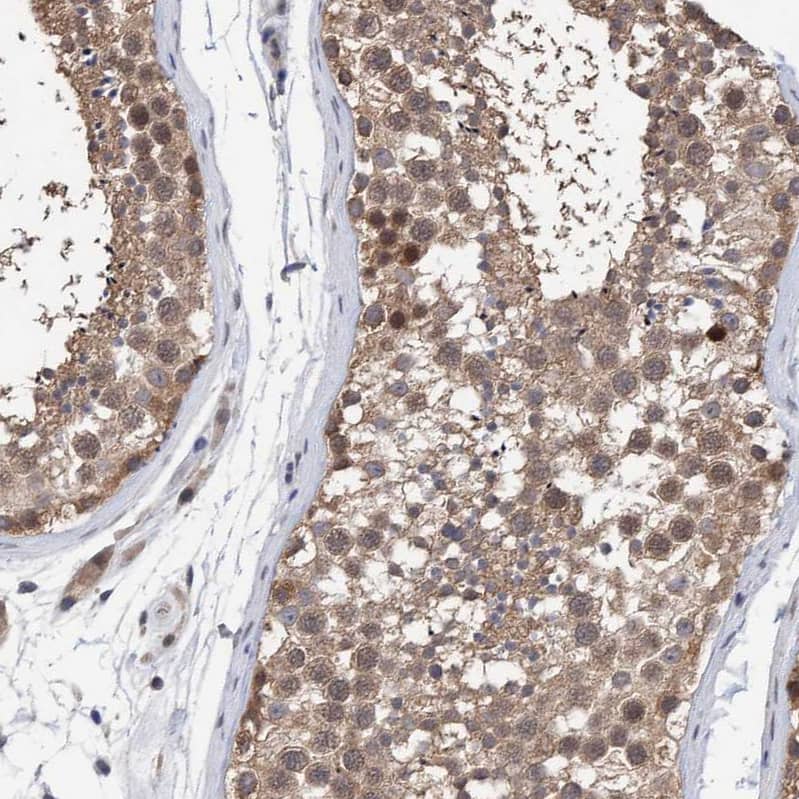

PURL Antibody - BSA Free

NBP1-84692

Species:

Hu

Applications:

WB, IHC

Host:

Rabbit Polyclonal